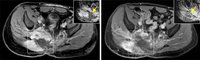

386. Ihre Spende wirkt: Weichgewebesarkom – Therapieansprechen vorhersagen und Resistenzmechanismen erklären

… Das Team um Dr. Heilig…